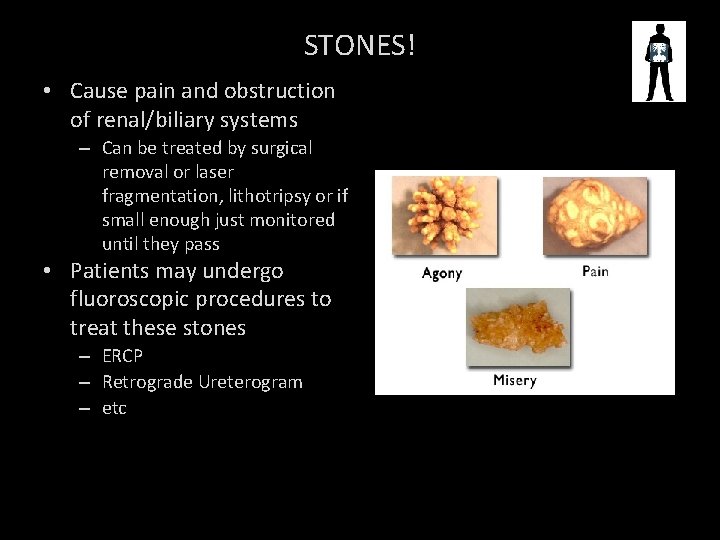

STONES! • Cause pain and obstruction of renal/biliary systems – Can be treated by surgical removal or laser fragmentation, lithotripsy or if small enough just monitored until they pass • Patients may undergo fluoroscopic procedures to treat these stones – ERCP – Retrograde Ureterogram – etc